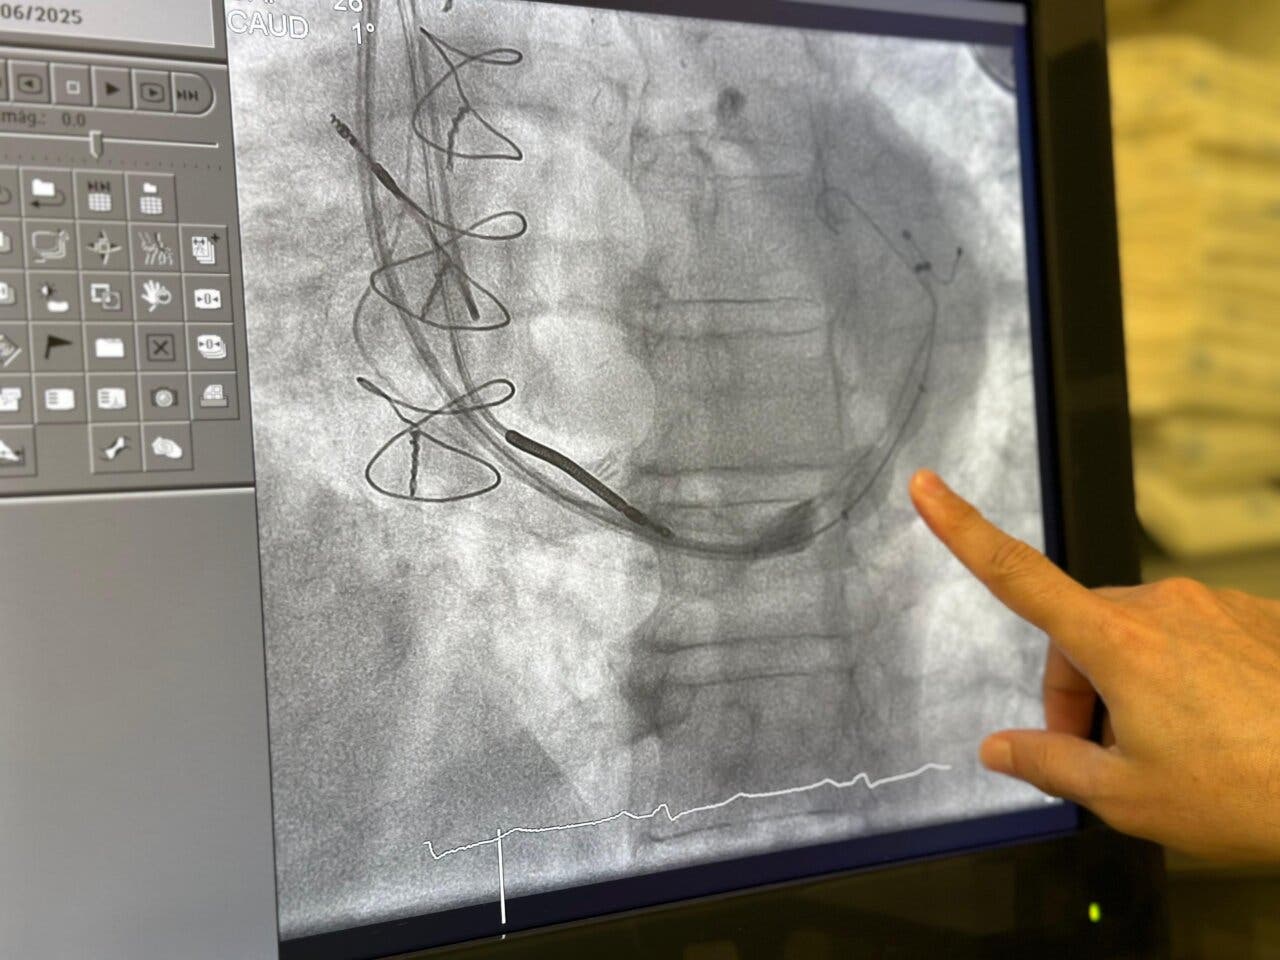

El Reducer, también llamado reductor del seno coronario (RSC), es un dispositivo pequeño con forma de reloj de arena. Se implanta en una vena del corazón para mejorar el riego sanguíneo en las zonas que no reciben suficiente oxígeno. Actúa aumentando la presión en el seno coronario, lo que ayuda a aliviar los síntomas.

El paciente intervenido tenía una enfermedad coronaria muy compleja. Había sido operado previamente con múltiples puentes aortocoronarios y llevaba varios stents implantados. Además, presentaba una afectación en vasos pequeños, ya no operables con cirugía ni angioplastia.

El caso se complicaba aún más porque el paciente ya disponía de un desfibrilador resincronizador, lo que supuso un reto técnico añadido. Aun así, la intervención fue un éxito y el paciente recibió el alta sin complicaciones en menos de 24 horas.